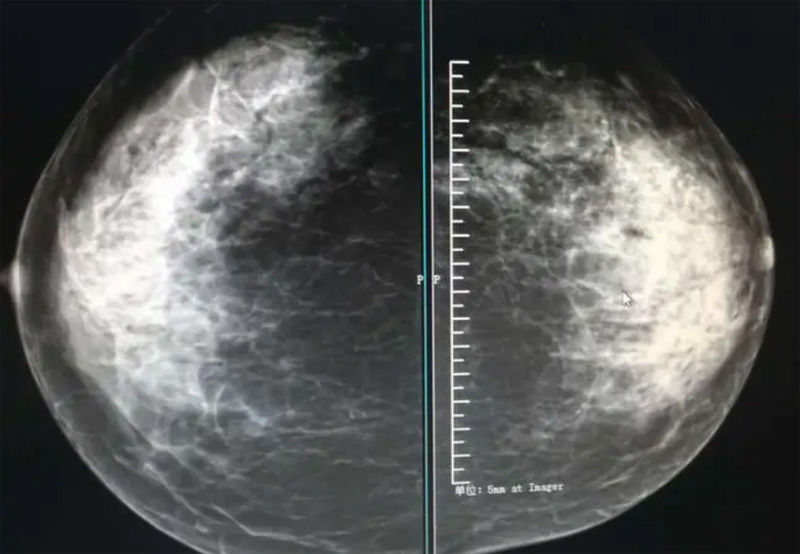

乳腺DR攝影體位有頭尾位及內(nèi)外側(cè)斜位,

乳房在片子的中央,乳頭切線位,可見小部分胸大肌,內(nèi)側(cè)乳腺組織應(yīng)全部包括在片中,外側(cè)乳腺組織盡可能包括在片中。一張好的MLO位圖像顯示如下:乳房被推向前上,乳腺實(shí)質(zhì)充分展開,胸大肌可見,較松弛,下緣達(dá)到乳頭水平,乳頭在切線位,部分腹壁包括在片中,但與下部乳腺分開,絕大部分乳腺實(shí)質(zhì)顯示在片中。乳腺組織外緣可見乳頭的輪廓;乳腺后方的脂肪組織被很好地顯示出來,乳房無皺褶。對(duì)于CC位及MLO位顯示不良或未包全的乳腺實(shí)質(zhì),可以根據(jù)病灶位置的不同選擇以下體位:外內(nèi)側(cè)位(LM)、內(nèi)外側(cè)位(ML)、內(nèi)側(cè)頭尾軸位(MCC)、外側(cè)頭尾軸位(LCC),尾葉位(CLEO)及乳溝位。在臨床實(shí)踐中,對(duì)于常規(guī)體位上發(fā)現(xiàn)的異常改變,可以進(jìn)一步采取一些特殊的攝影技術(shù),包括局部加壓攝影、放大攝影或局部加壓放大攝影技術(shù)。